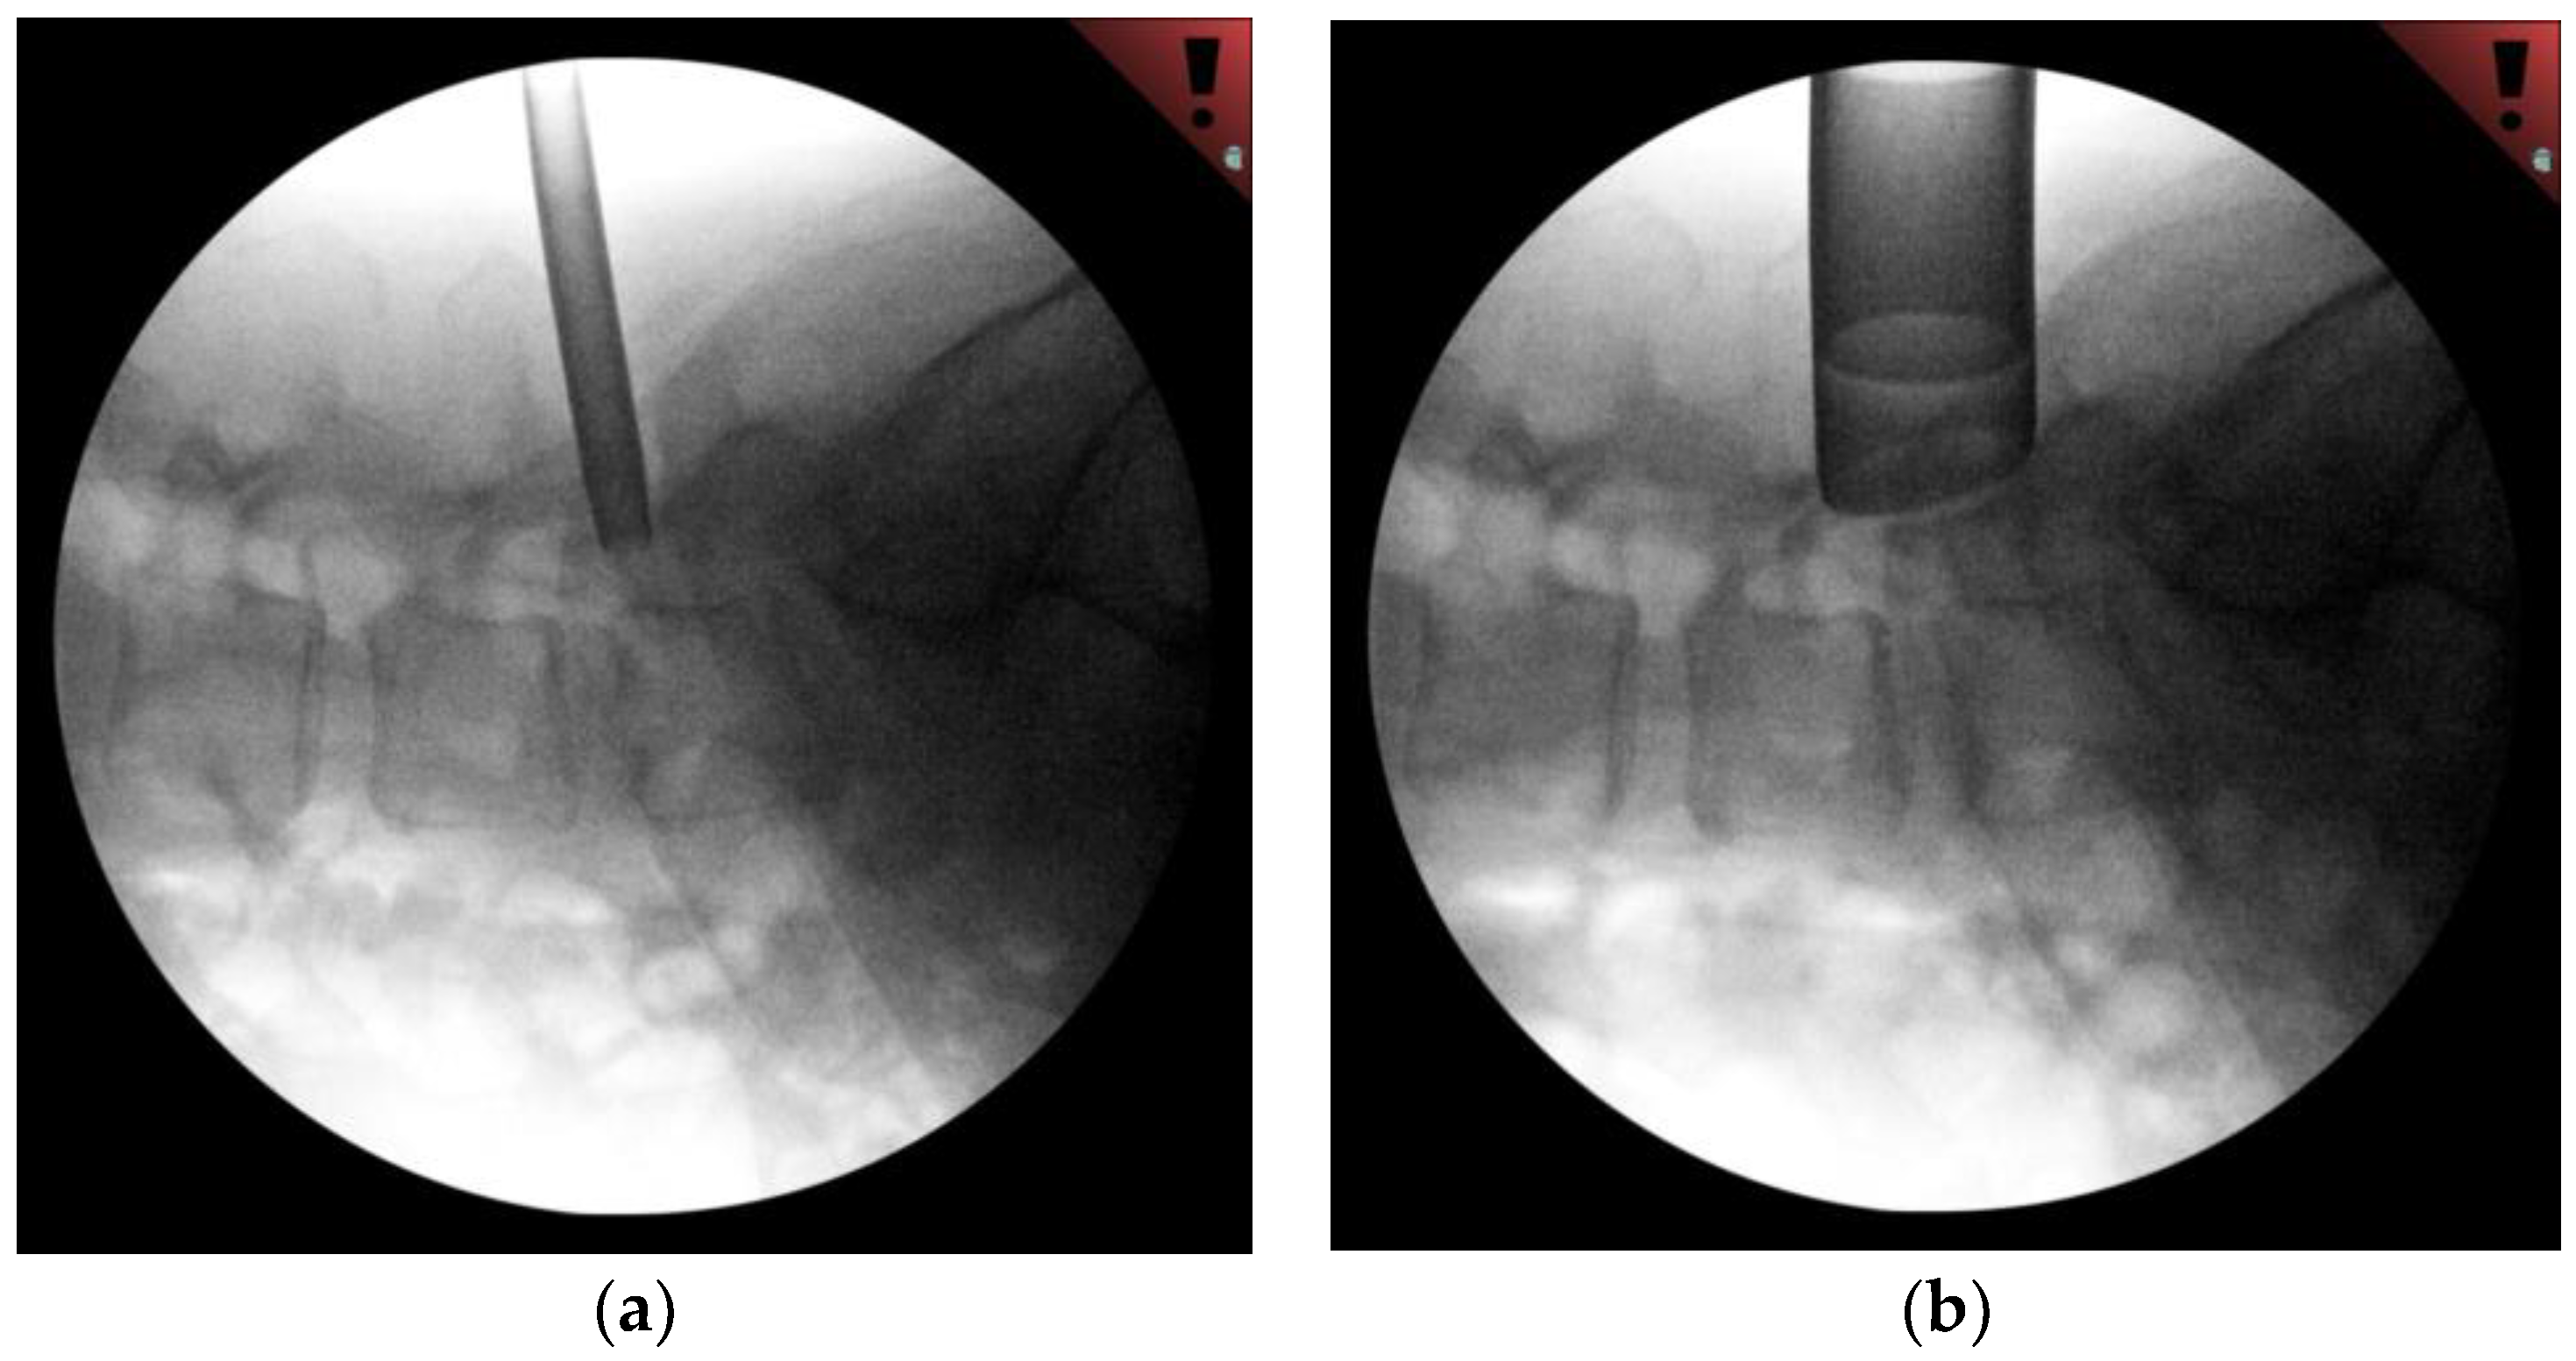

2.2. Technical Description